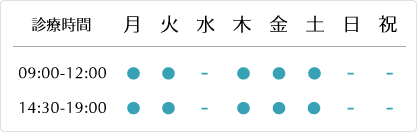

治療前後の模型比較

いずみ歯科矯正歯科医院では既成の矯正装置を利用するのではなく、一歯ずつブラケットという矯正装置を装着する事でその人にあった本格的な矯正治療をしています。

このお子さんは上下顎の成長バランスが悪く、咬み合わせも低いので、歯並びにかなり悪影響を与えていました。このような方は、子供の時の顎の成長期に歪みを改善しておくと後の治療が楽になります。

当院の子供の矯正によって、上下顎はバランスよく成長し、歯槽骨のカーブも緩やかになり、歯並びだけでなく口腔機能も改善されました。

初診時10歳9カ月~終了時13歳10カ月